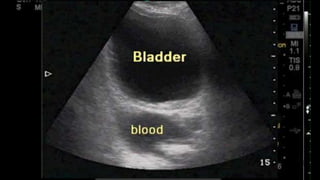

•FAST (Focused Abdominal Sonogram for Trauma)

FAST